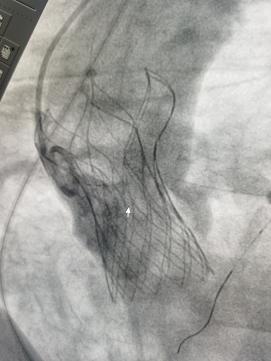

手术当天,心内科团队预先放置左冠导丝,进而左冠脉开口可以不受任何影响。在各专业团队的合作下,患者TAVR手术顺利完成。整个过程患者生命体征平稳,经术中食道超声检查提示,人工瓣膜功能良好,解决了主动脉瓣重度狭窄问题,冠脉血流通畅,手术取得圆满成功。术后第一天,患者由重症监护病房转回普通病房。